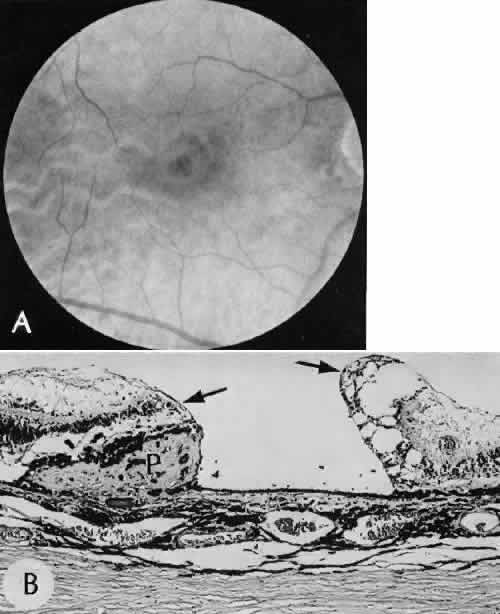

A flat anterior chamber is characterized by anterior displacement of the iris to near or in actual contact with the posterior surface of the cornea. The most common cause is leakage of aqueous along one of the suture tracks. Prolonged decompression of the anterior chamber increases the risk of synechiae formation and intractable secondary closed-angle glaucoma. Corneal endothelial damage may result in bullous keratopathy. Choroidal edema (choroidal hydrops or detachment) (Fig. 31) may be associated with a flat anterior chamber and may potentiate the condition. The choroidal edema will slow or stop aqueous production by the ciliary body, further delaying reformation of the anterior chamber. The histologic characteristics of choroidal edema consist of spreading of the choroidal tissue in a fanlike configuration and eosinophilic fluid filling the intervening spaces. The edema fluid may be lost in processing, leaving multiple apparently empty spaces.

Fig. 31. A case of choroidal detachment. A. By fundus reflex, a large dome-shaped mass can be seen originating from the choroid. The differential diagnosis would include uveal malignant melanoma. In this case, the clinical findings were due to choroidal detachment from the sclera because of fluid accumulating in the suprachoroidal space following cataract surgery. B. The histologic section from another case of choroidal detachment illustrates the location (arrow) and extent of the detachment. In this case the detachment extends to the region of the ciliary body limited anteriorly by the attachment of the choroid to the scleral spur. The displacement of the ciliary body will result in apparent shallowing of the anterior chamber. (Hematoxylin-eosin stain; × 6.)

Retinal detachment (Fig. 42) occurs in approximately 2% to 8% of intracapsular cataract surgeries, compared with approximately 0.0013% in the general population. The incidence of retinal detachment after extracapsular cataract extraction and posterior chamber lens implantation ranges between 0.6% and 1.5%.121 Vitreous loss increases the incidence of postoperative detachments, particularly if there is vitreous incarceration into the cataract wound. The character of the retinal detachment is independent of the type of cataract surgery or the type of intraocular lens implanted. However, a lower incidence of proliferative vitreoretinopathy appears in cases of extracapsular cataract extraction than was formerly seen with intracapsular cataract extraction.

Fig. 42. Two cases of retinal detachment following cataract extraction. A. Retinal detachment was identified 4 weeks after cataract extraction. Fixed retinal folds indicate that the situation is inoperable, so no surgical repair was attempted. The anterior chamber angle has become occluded because of neovascularization associated with ischemic retina. B. Retinal detachment was identified 5 weeks after cataract extraction. Two attempts at surgical repair failed. The large equatorial cystic spaces indicated the presence of a scleral-buckling element. The actual material of the sponge and buckle has been lost during tissue processing. The cystic nature of the detached retinal tissue indicates that there was an extended time between the last retinal reattachment attempt and enucleation. In this case, peripheral anterior synechiae are present. The indication for enucleation was most likely a blind painful eye due to secondary glaucoma and reactive uveitis. (Hematoxylin-eosin stain; × 3.)